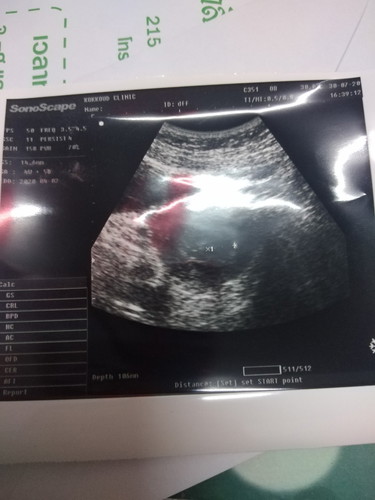

ขอดูใบซาวน์ของแม่ๆอายุครภภ์4วีคหน่อยค่ะเจอตัวร้องกันยังคะ

อายุครรภ์4วีค5วัน ใครเจอตัวน้องบ้างค่ะ

ยังไม่เจอหรอกจ้า อายุครรภ์ยังน้อยมาก รอสัก 6-7 วีค ค่อยซาวด์อีกทีก็ได้จ้า (แอบกระซิบว่าทางช่องคลอดเห็นง่ายกว่าหน้าท้องนะคะ)

ยังจ้า บ้านนี้เคยซาวด์ตอน4wเห็นแค่ถุงการตั้งครรภ์ เห็นตัวน้องกับหัวใจเต้นตอน9w ปัจจุบันคลอดน้องแล้วจ้า